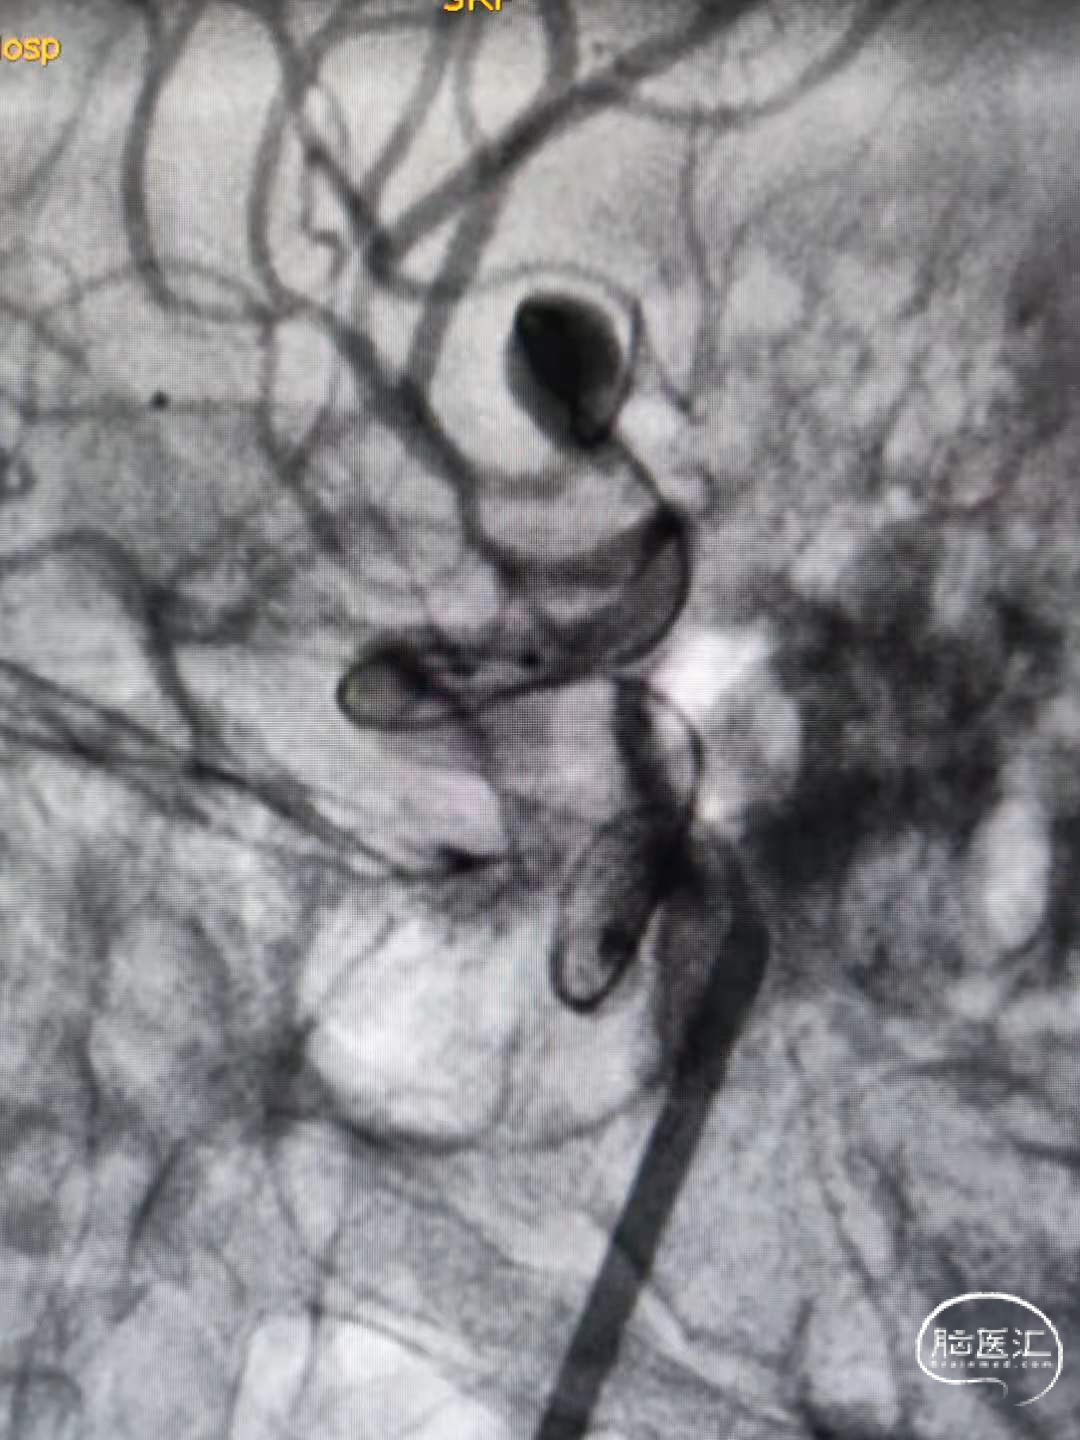

脑血管造影显示右侧大脑中动脉分叉部宽颈动脉瘤,约7.4-7.0-6mm大小。动脉瘤为不规则形态,右侧中动脉上下支干均受累,其中上支干纤细约1.0mm,自瘤体近瘤颈处发出。

术前影像

1、与术前分析的一致,由于上支干与M1成角以及瘤颈很宽等因素,微导管超选上支干很困难。最终选择微导丝及微导管瘤体内成袢进入上支干很远后再缓慢逐步回撤微导管解袢。(该步骤风险很大,因为动脉瘤破裂点在瘤顶部,操作时要对微导丝及微导管有精确的掌控能力)。术中使用SL-10微导管及Synchro-14导丝。